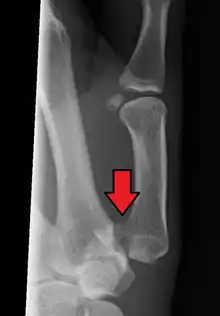

Bennett fracture is a type of partial broken finger involving the base of the thumb, and extends into the carpometacarpal (CMC) joint.[1]

This intra-articular fracture is the most common type of fracture of the thumb, and is nearly always accompanied by some degree of subluxation or frank dislocation of the carpometacarpal joint.

In the case of the Bennett fracture, the proximal metacarpal fragment remains attached to the anterior oblique ligament, which in turn is attached to the tubercle of the trapezium bone of the CMC joint. This ligamentous attachment ensures that the proximal fragment remains in its correct anatomical position.

The distal fragment of the first metacarpal bone possesses the majority of the articular surface of the first CMC joint. Unlike the proximal fracture fragment, strong ligaments and muscle tendons of the hand tend to pull this fragment out of its correct anatomical position.

Though these fractures commonly appear quite subtle or even inconsequential on radiographs, they can result in severe long-term dysfunction of the hand if left untreated. In his original description of this type of fracture in 1882, Bennett stressed the need for early diagnosis and treatment in order to prevent loss of function of the thumb CMC joint, which is critical to the overall function of the hand.[4]